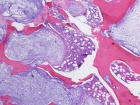

22 year old woman c/o firm mass on rib under left breast that is increasing in size and becoming painful in the last couple of months

Zoom image: Cell stain Cell stain.